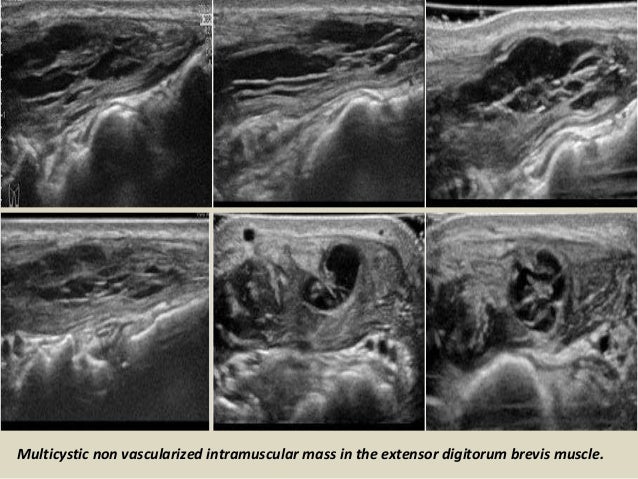

Multicystic non vascularized intramuscular mass in the extensor digitorum brevis muscle.

42. 42. Multicystic non vascularized intramuscular mass in the extensor digitorum brevis muscle.